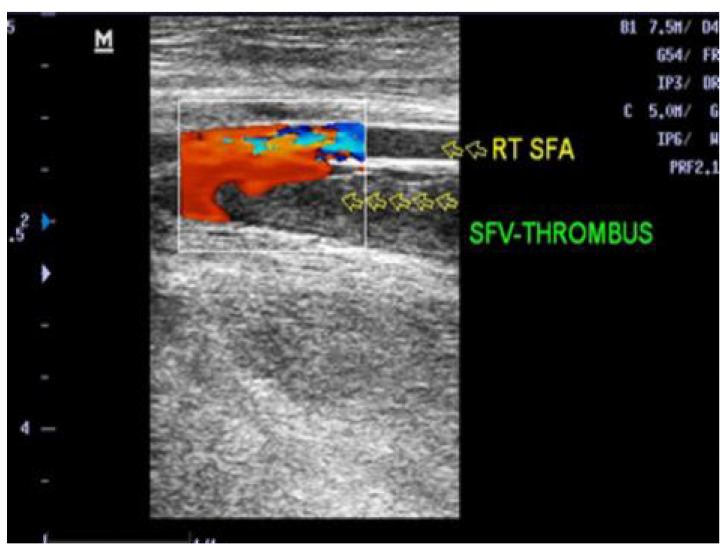

Case presentations: We had an equal number of males and females of the eight patients. Their ages ranged from 20 to 80 years. Five patients presented with bilateral lower limbs Deep vein thrombosis (DVT) of which one had a pulmonary embolism. Two other patients had extensive left femoral DVT and one had extensive IVC, iliac, femoral, and popliteal veins thrombosis. The medical records of seven patients, who had IVC filter placement in our department, were reviewed. The IVC filter was deployed with the aid of a C-arm fluoroscopic unit. In a single case, access was secured via an indwelling dialysis catheter.